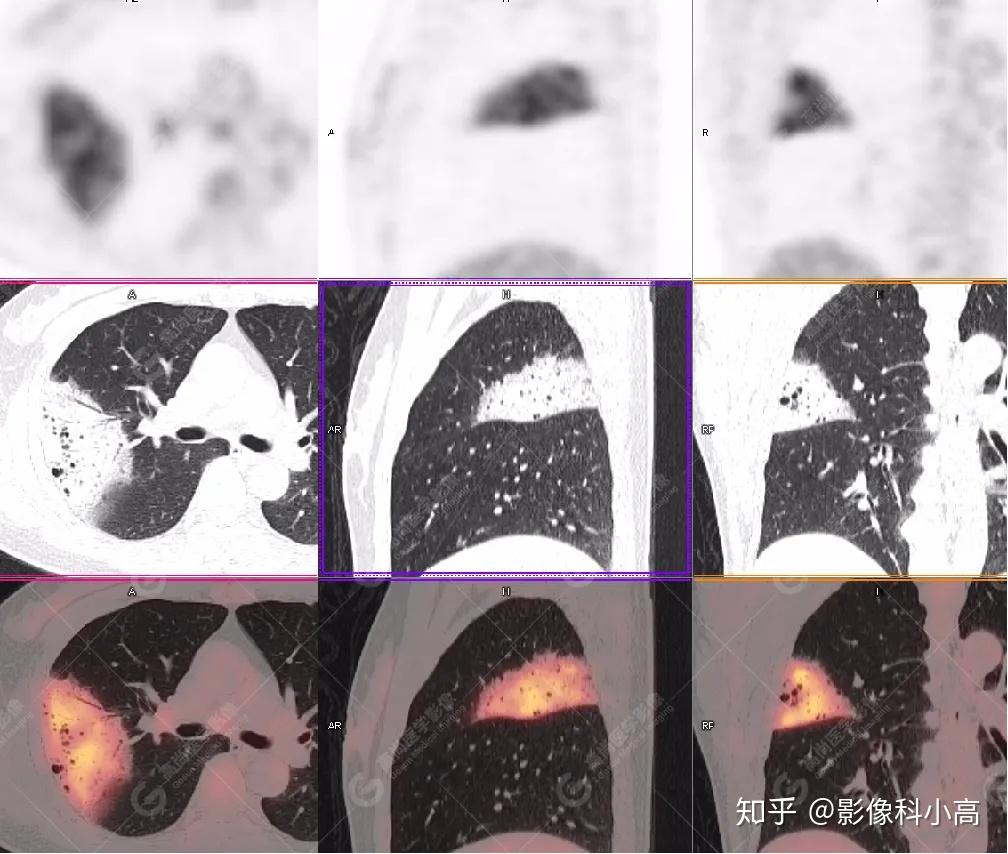

神经元特异性烯醇化酶NSE偏高可能与以下因素相关,需结合临床综合判断1 神经内分泌肿瘤NSE是神经内分泌肿瘤的标志物之一,小细胞肺癌和神经母细胞瘤等肿瘤细胞会大量分泌NSE,导致其水平显著升高此类患者需通过影像学检查...